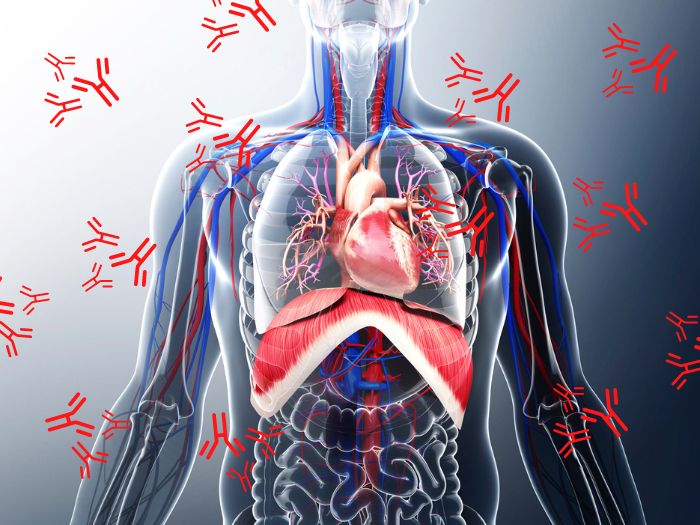

Аутоімунний протокол (АІП) – відсіч аутоімунним захворюванням

Маєш аутоімунні захворювання і самостійно не можеш покращити свій стан?

Навчально-методичний посібник Аутоімунний протокол у E-book форматі – твій помічник у боротьбі з проявами запалення та аутоімунними захворюваннями. Покрокові рекомендації та двотижневе меню, яке було розроблене нутриціологом з 10-ти річним досвідом роботи.